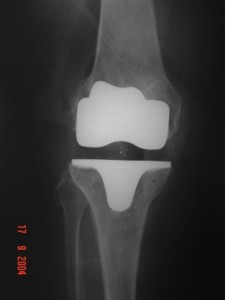

Radyoloji; Ayakta basarak çekilen grafiler, gerekirse MRI görüntüleriniz, kemik yapınız ve yumuşak dokularınız hakkında bilgi verecektir.

Ameliyatta kıkırdağın ve kemiğin hasarlı kısımları çıkartılacak, bacaktaki deformasyon düzeltilecek, yumuşak doku ve ligamentler dengelenecek, çıkartılmış olan kemik yüzeylere kemik çimentosu yardımı ile metal ve polietilen (plastik ara yüzey) implantlar yerleştirilecektir. Daha sonra yumuşak dokular ve cilt dikilecek, eklemde biriken sıvı ve kanı boşaltmak için konulan dren bir gün sonra çıkartılacaktır.